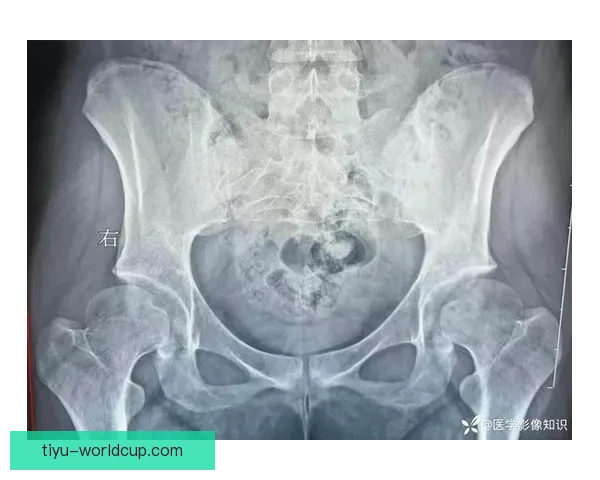

伤病成因剖析entity["athlete","威廉姆斯","athlete injury case"]的耻骨炎并非偶然。长期高强度对抗、频繁变向与负荷叠加,使耻骨联合区域承压过大,炎症逐步累积,最终演变为影响核心力量的顽疾。

更关键的是,赛程密集与恢复窗口不足放大了风险。即便短期止痛复出,深层炎症仍难以根治,反复拉扯让伤情进入慢性阶段,直接为“毁赛季”埋下伏笔。

速度下滑困局耻骨炎对爆发力的侵蚀最为致命。威廉姆斯起步与横移明显变慢,原本依赖的第一步优势被削弱,比赛中只能以“半速”应对,攻防两端效率同步下滑。